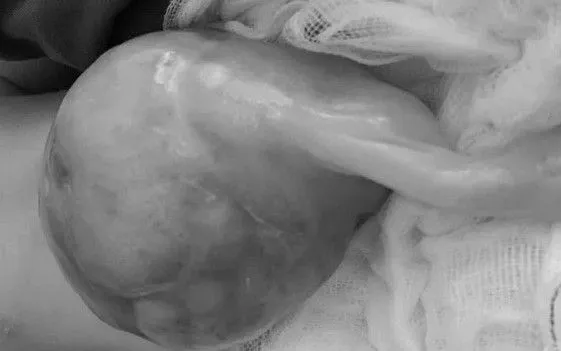

VTV.vn - Bệnh viện Sản Nhi Nghệ An vừa cứu sống bé sơ sinh mắc thoát vị rốn khổng lồ 15x14x13 cm, nội tạng sa ra ngoài ngay khi chào đời.

Bệnh nhi L.H.D., chào đời với khối thoát vị rốn kích thước lên tới 15x14x13 cm, trong đó gan và ruột sa hoàn toàn ra ngoài thành bụng. Dị tật được phát hiện từ tuần thai thứ 13 qua siêu âm, nên ngay sau sinh, bệnh nhi được đặt nội khí quản và chuyển thẳng đến Khoa Hồi sức tích cực Ngoại để xử trí.

Với những trường hợp nhẹ, khối thoát vị có thể tự xẹp. Tuy nhiên, nếu nội tạng chui qua lỗ thoát vị khiến bụng chướng, có nguy cơ tắc nghẽn, hoại tử ruột, cần can thiệp cấp cứu. Trường hợp của bệnh nhi này là khối thoát vị lớn nhất từ trước đến nay mà khoa tiếp nhận xử trí.

Sau 71 ngày điều trị liên tục, bệnh nhi đáp ứng tốt, khối thoát vị đã dần hóa da, chức năng hô hấp ổn định và được xuất viện trong tình trạng an toàn.

Theo BSCKII. Tạ Thị Quỳnh Anh, phẫu thuật là phương pháp điều trị duy nhất đối với thoát vị rốn. Thời điểm lý tưởng là trong 6 giờ đầu sau sinh, nhưng chỉ áp dụng nếu khối thoát vị không quá lớn (đường kính vòng rốn dưới 6 cm) và đóng bụng không làm tăng áp lực ổ bụng. Với trường hợp của bé L.H.D., do khối thoát vị quá khổng lồ và thể trạng trẻ còn non yếu, việc can thiệp phải trì hoãn để chờ quá trình biểu bì hóa hoàn chỉnh trước khi đưa dần các tạng trở lại ổ bụng.